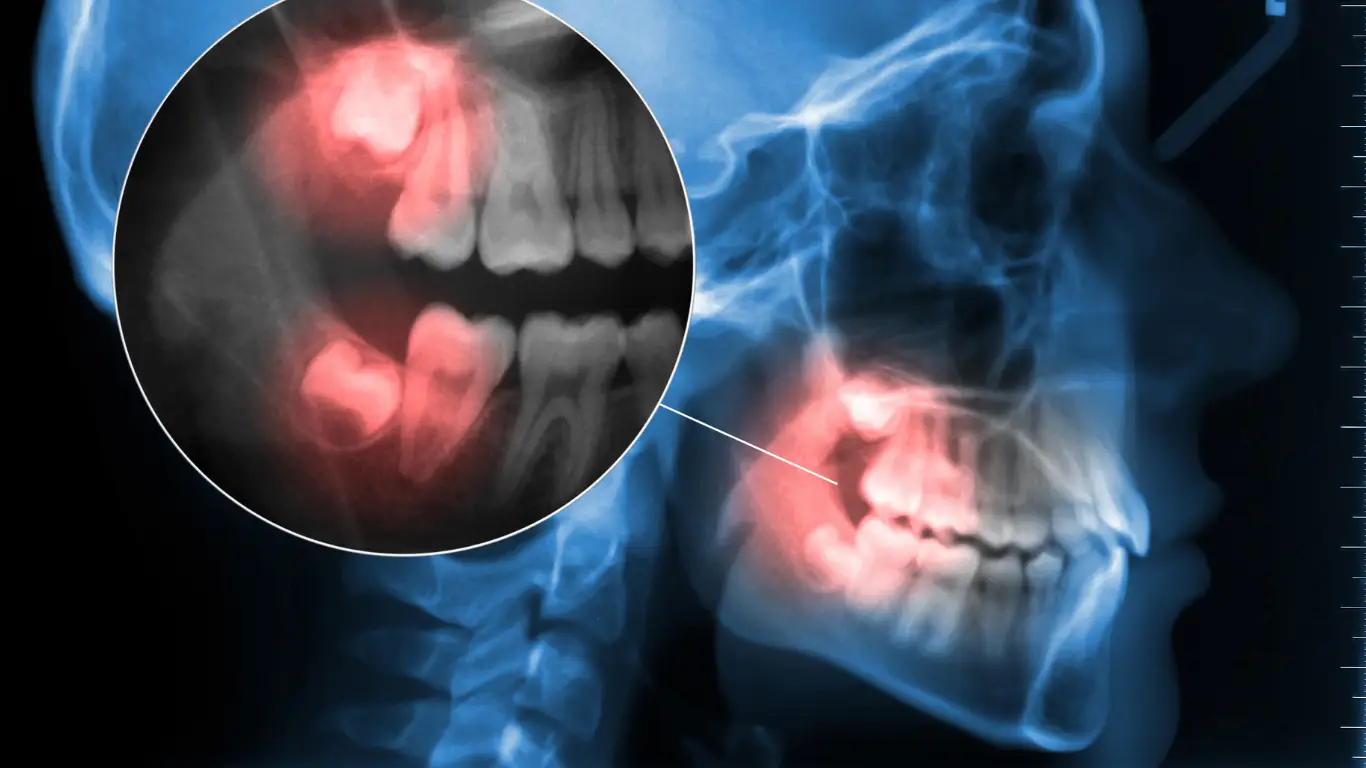

Wisdom Tooth Removal Recovery Timeline: What to Expect After Extraction

It’s normal to be nervous after having your wisdom teeth removal, but knowing how to heal can help. Prepare for the healing journey by knowing what to expect at each stage. From the first few days following surgery to the final stage of healing, this wisdom teeth recovery timeline guides you through symptoms, post-care, and recovery.